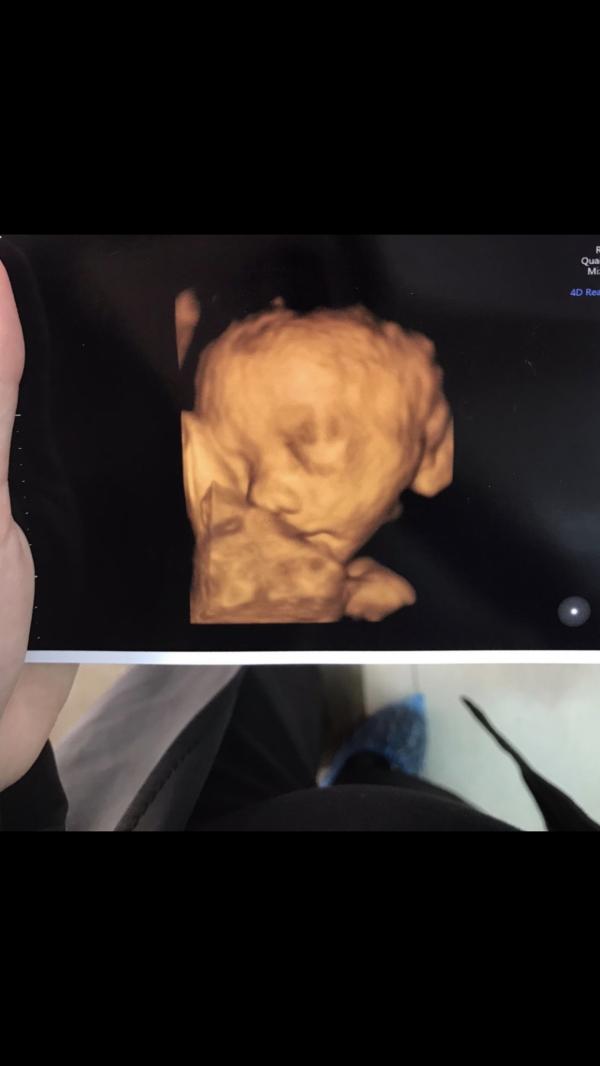

Девочки,поставили многоводие на 38 недели. Иаж был 24,7. Влияет ли как-то на плод многоводие? Завтра 40 неделя. На приём к гинекологу только послезавтра. Может ли быть это причиной укладывания и стимуляции родового процесса? Вес ребёнка некрупный